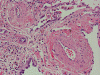

At scanning magnification (Panel A), the lung parenchyma is replaced by some coalescing fibrous nodules. The degree of involvement is variable at different fragments (Panel B and C). In the less affected areas, there are some fibrotic thickening of the septa (Panel C). In some areas, the changes are minimal and the pleural appear to be uninvolved (Panel D and E). In low to medium magnifications, these nodules of fibrosis contains a large number of hemosiderin laden macrophages (Panel F and G) admixed with fibrous tissue. The diagnostic tissue, however, is present in areas with increased cellularity. In these areas, there is a background of cells with a moderate amount of cytoplasm and bland nuclei. Some of these nuclei have kidney shape (arrow in Panel H). In some areas, many of the nuclei have a deep nuclear groove that resemble a coffee bean (arrow in Panel I). In the third type of areas, the nuclear grooving is not distinct (Panel J). Prominent eosinophilic infiltrations are almost always present. Immunohistochemistry on CD1a revealed many positive cells (Panel L). Also present in the specimen are multiple small blood vessels with thickened intima (Panel K). A Movat pentachrome stain demonstrates an internal elastic layer in these vessels and confirms that these are arteries (Panel M and N).

In the early stage of PLCH, there are interstitial infiltrates composed of LCs, lymphocytes, macrophages, eosinophils, plasma cells and fibroblasts 4. The infiltrates enlarge to form nodules centered on the small airways. Brown pigmented macrophages (smokers macrophages) are present in and around the nodules. Eosinophils tend to localize at the innermost layer of the nodules, where LCs can be most easily found in the thickened interstitium. Associated patchy interstitial and airspace organization or respiratory bronchiolitis may be present. Other smoking related changes are also common. Cavitation often occurs within the nodules which represents either an airway remenant or de novo cavitation as the inflammatory infiltrate enlarges. There is centripetal replacement of the nodules by fibroblasts which produce the classic stellate lesions of PLCH. As the disease progresses, the number of nodules, cavitary granulomas and fibrotic scars increase in number.